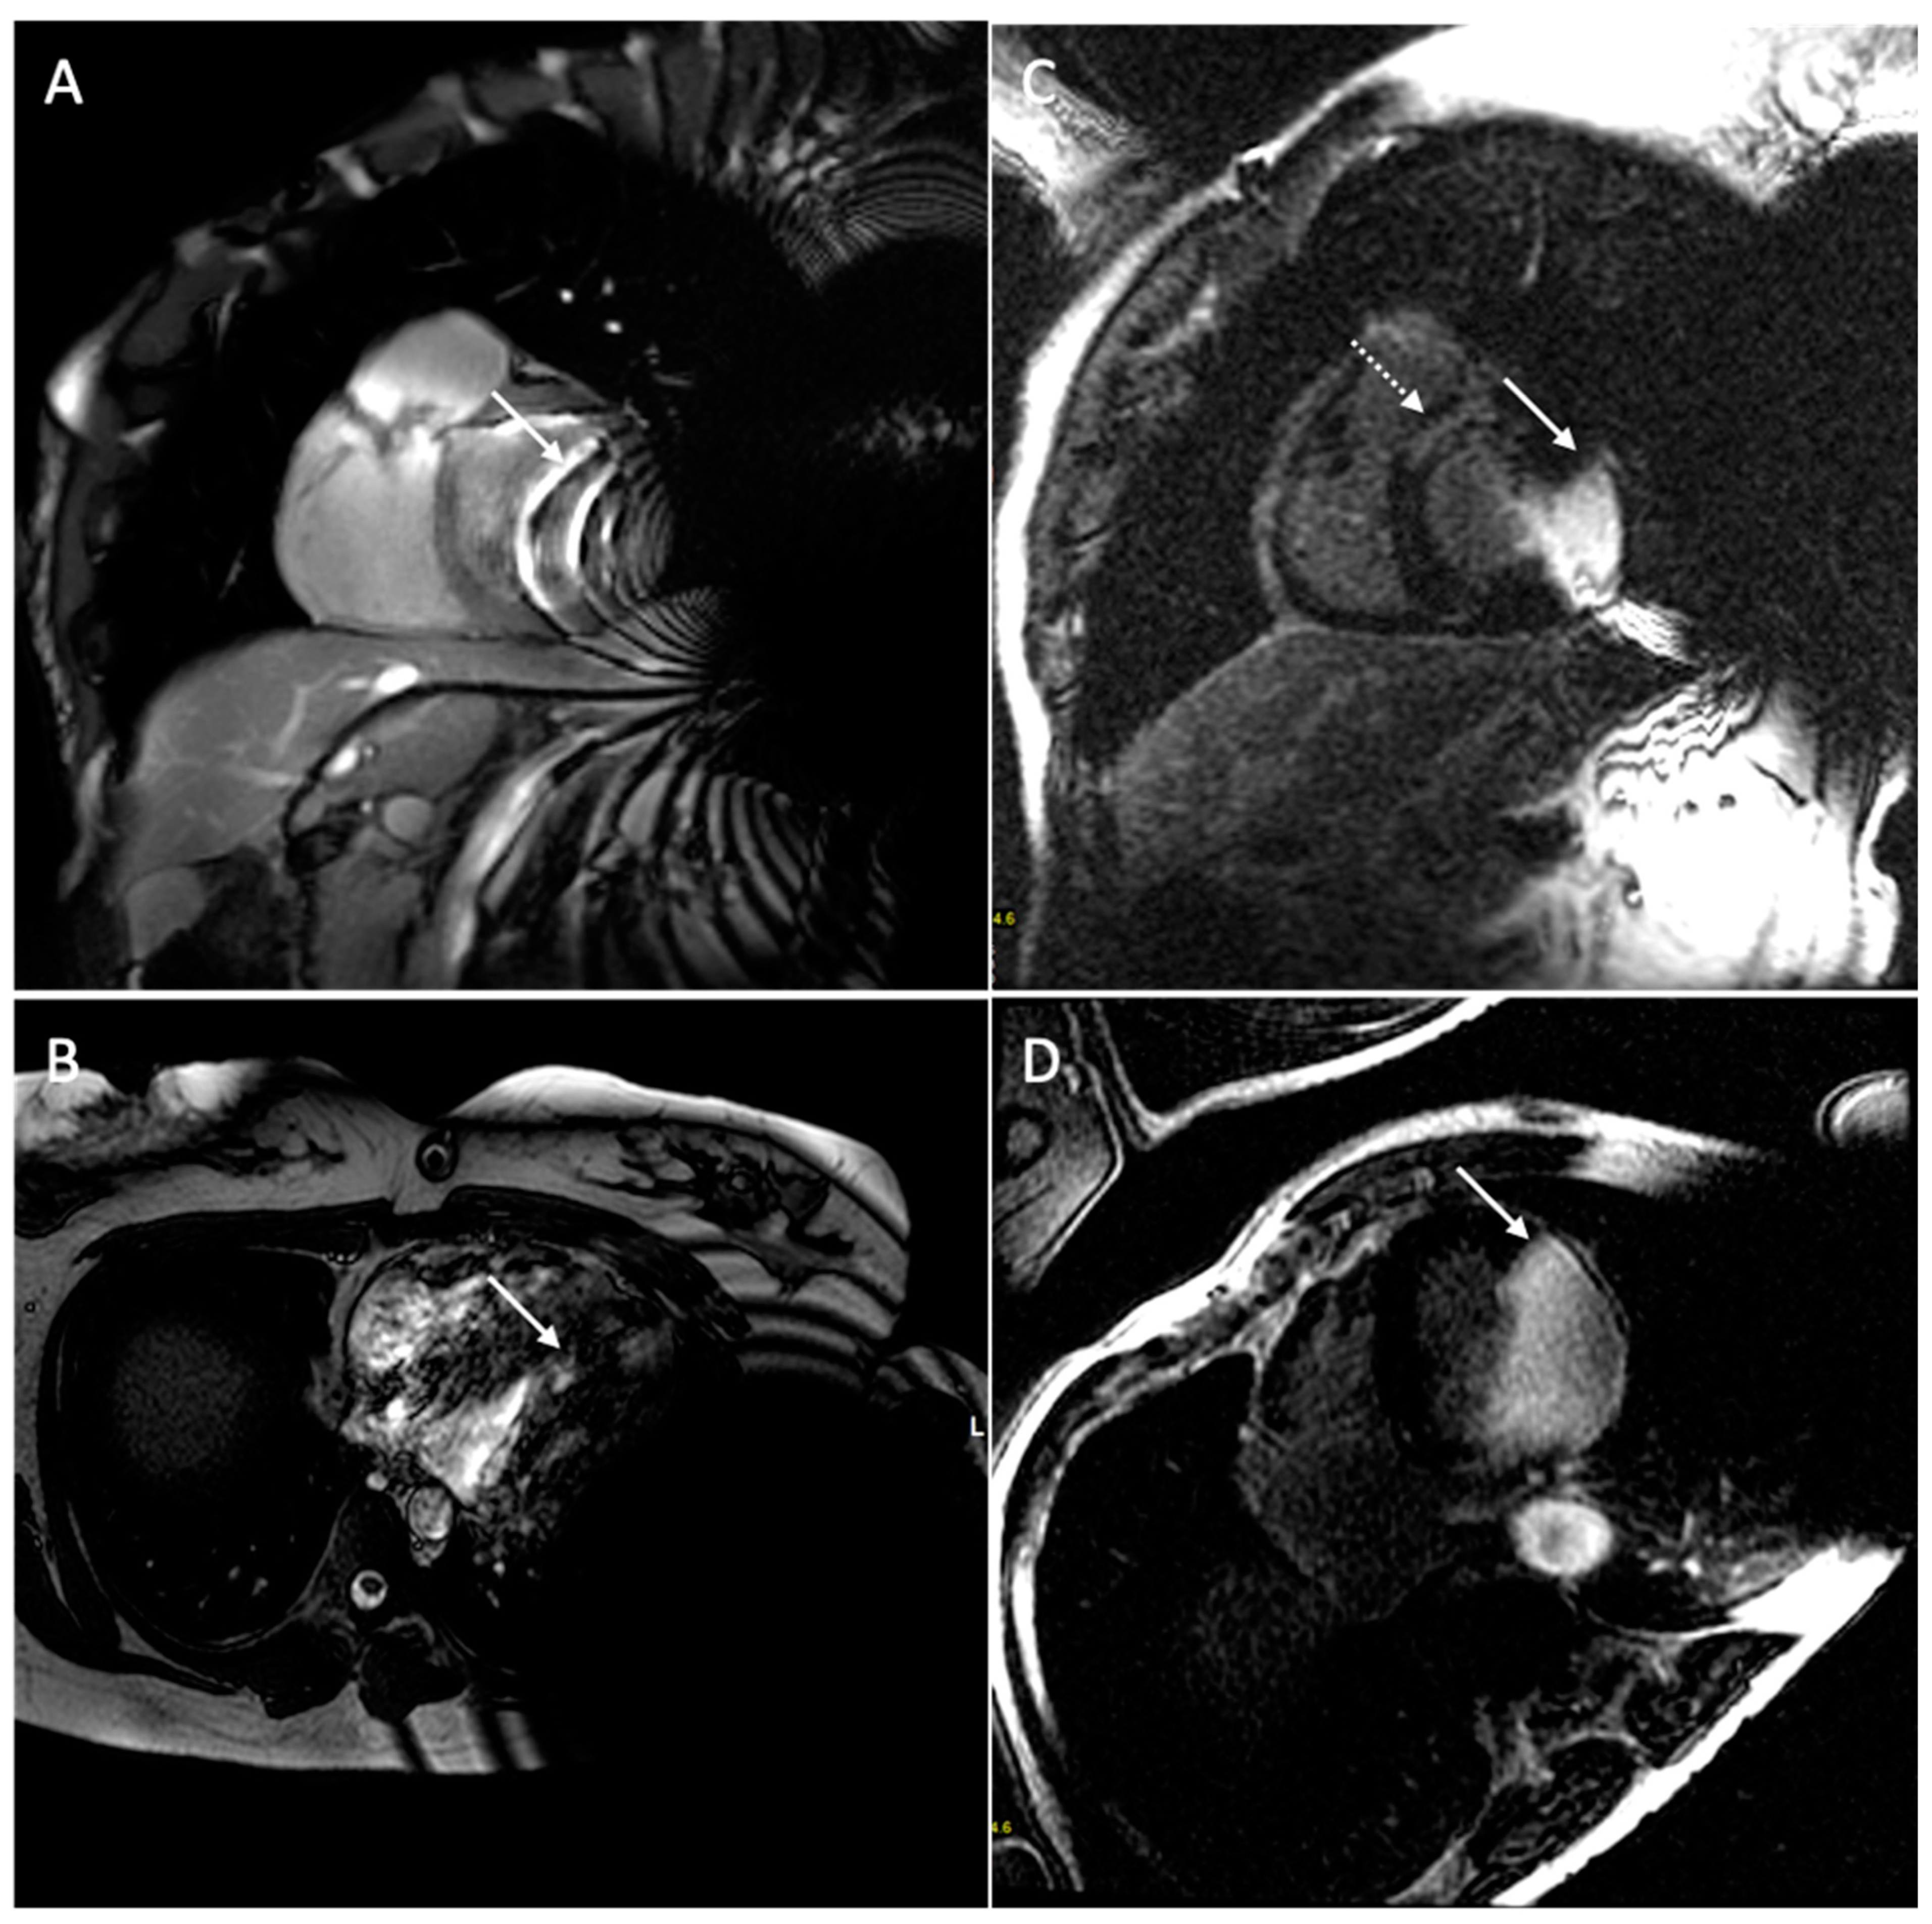

- Vuorinen, A.-M.; Lehmonen, L.; Karvonen, J.; Holmström, M.; Kivistö, S.; Kaasalainen, T. Reducing cardiac implantable electronic device–induced artefacts in cardiac magnetic resonance imaging. Eur. Radiol. 2022, 33, 1229–1242. [Google Scholar] [CrossRef] [PubMed]

- Runge, M.; Ibrahim, E.-S.H.; Bogun, F.; Attili, A.; Mahani, M.G.; Pang, Y.; Horwood, L.; Chenevert, T.L.; Stojanovska, J. Metal Artifact Reduction in Cardiovascular MRI for Accurate Myocardial Scar Assessment in Patients with Cardiac Implantable Electronic Devices. Am. J. Roentgenol. 2019, 213, 555–561. [Google Scholar] [CrossRef]

- Ibrahim, E.-S.H.; Runge, M.; Stojanovska, J.; Agarwal, P.; Ghadimi-Mahani, M.; Attili, A.; Chenevert, T.; Harder, C.D.; Bogun, F. Optimized cardiac magnetic resonance imaging inversion recovery sequence for metal artifact reduction and accurate myocardial scar assessment in patients with cardiac implantable electronic devices. World J. Radiol. 2018, 10, 100–107. [Google Scholar] [CrossRef]

| Types of Artifacts | Factors that Influence Artifacts | High Artifact | Low Artifact |

|---|---|---|---|

| Signal loss artifact Hyperintensity artifact | CIED’s dimension | Large device | Small device |

| CIED’s position | Left-sided implantation | Right-sided implantation | |

| Magnetic susceptibility | High ferromagnetic component | Low ferromagnetic components | |

| High static MF | Low static MF | ||

| Distance from the region of interest | Proximity to the heart | Elevate the patient’s arm | |

| MRI sequences used | Cine SSFP | SGE sequences | |

| LGE sequence with a bandwidth of about 1 kHz | LGE sequence with a wide bandwidth |